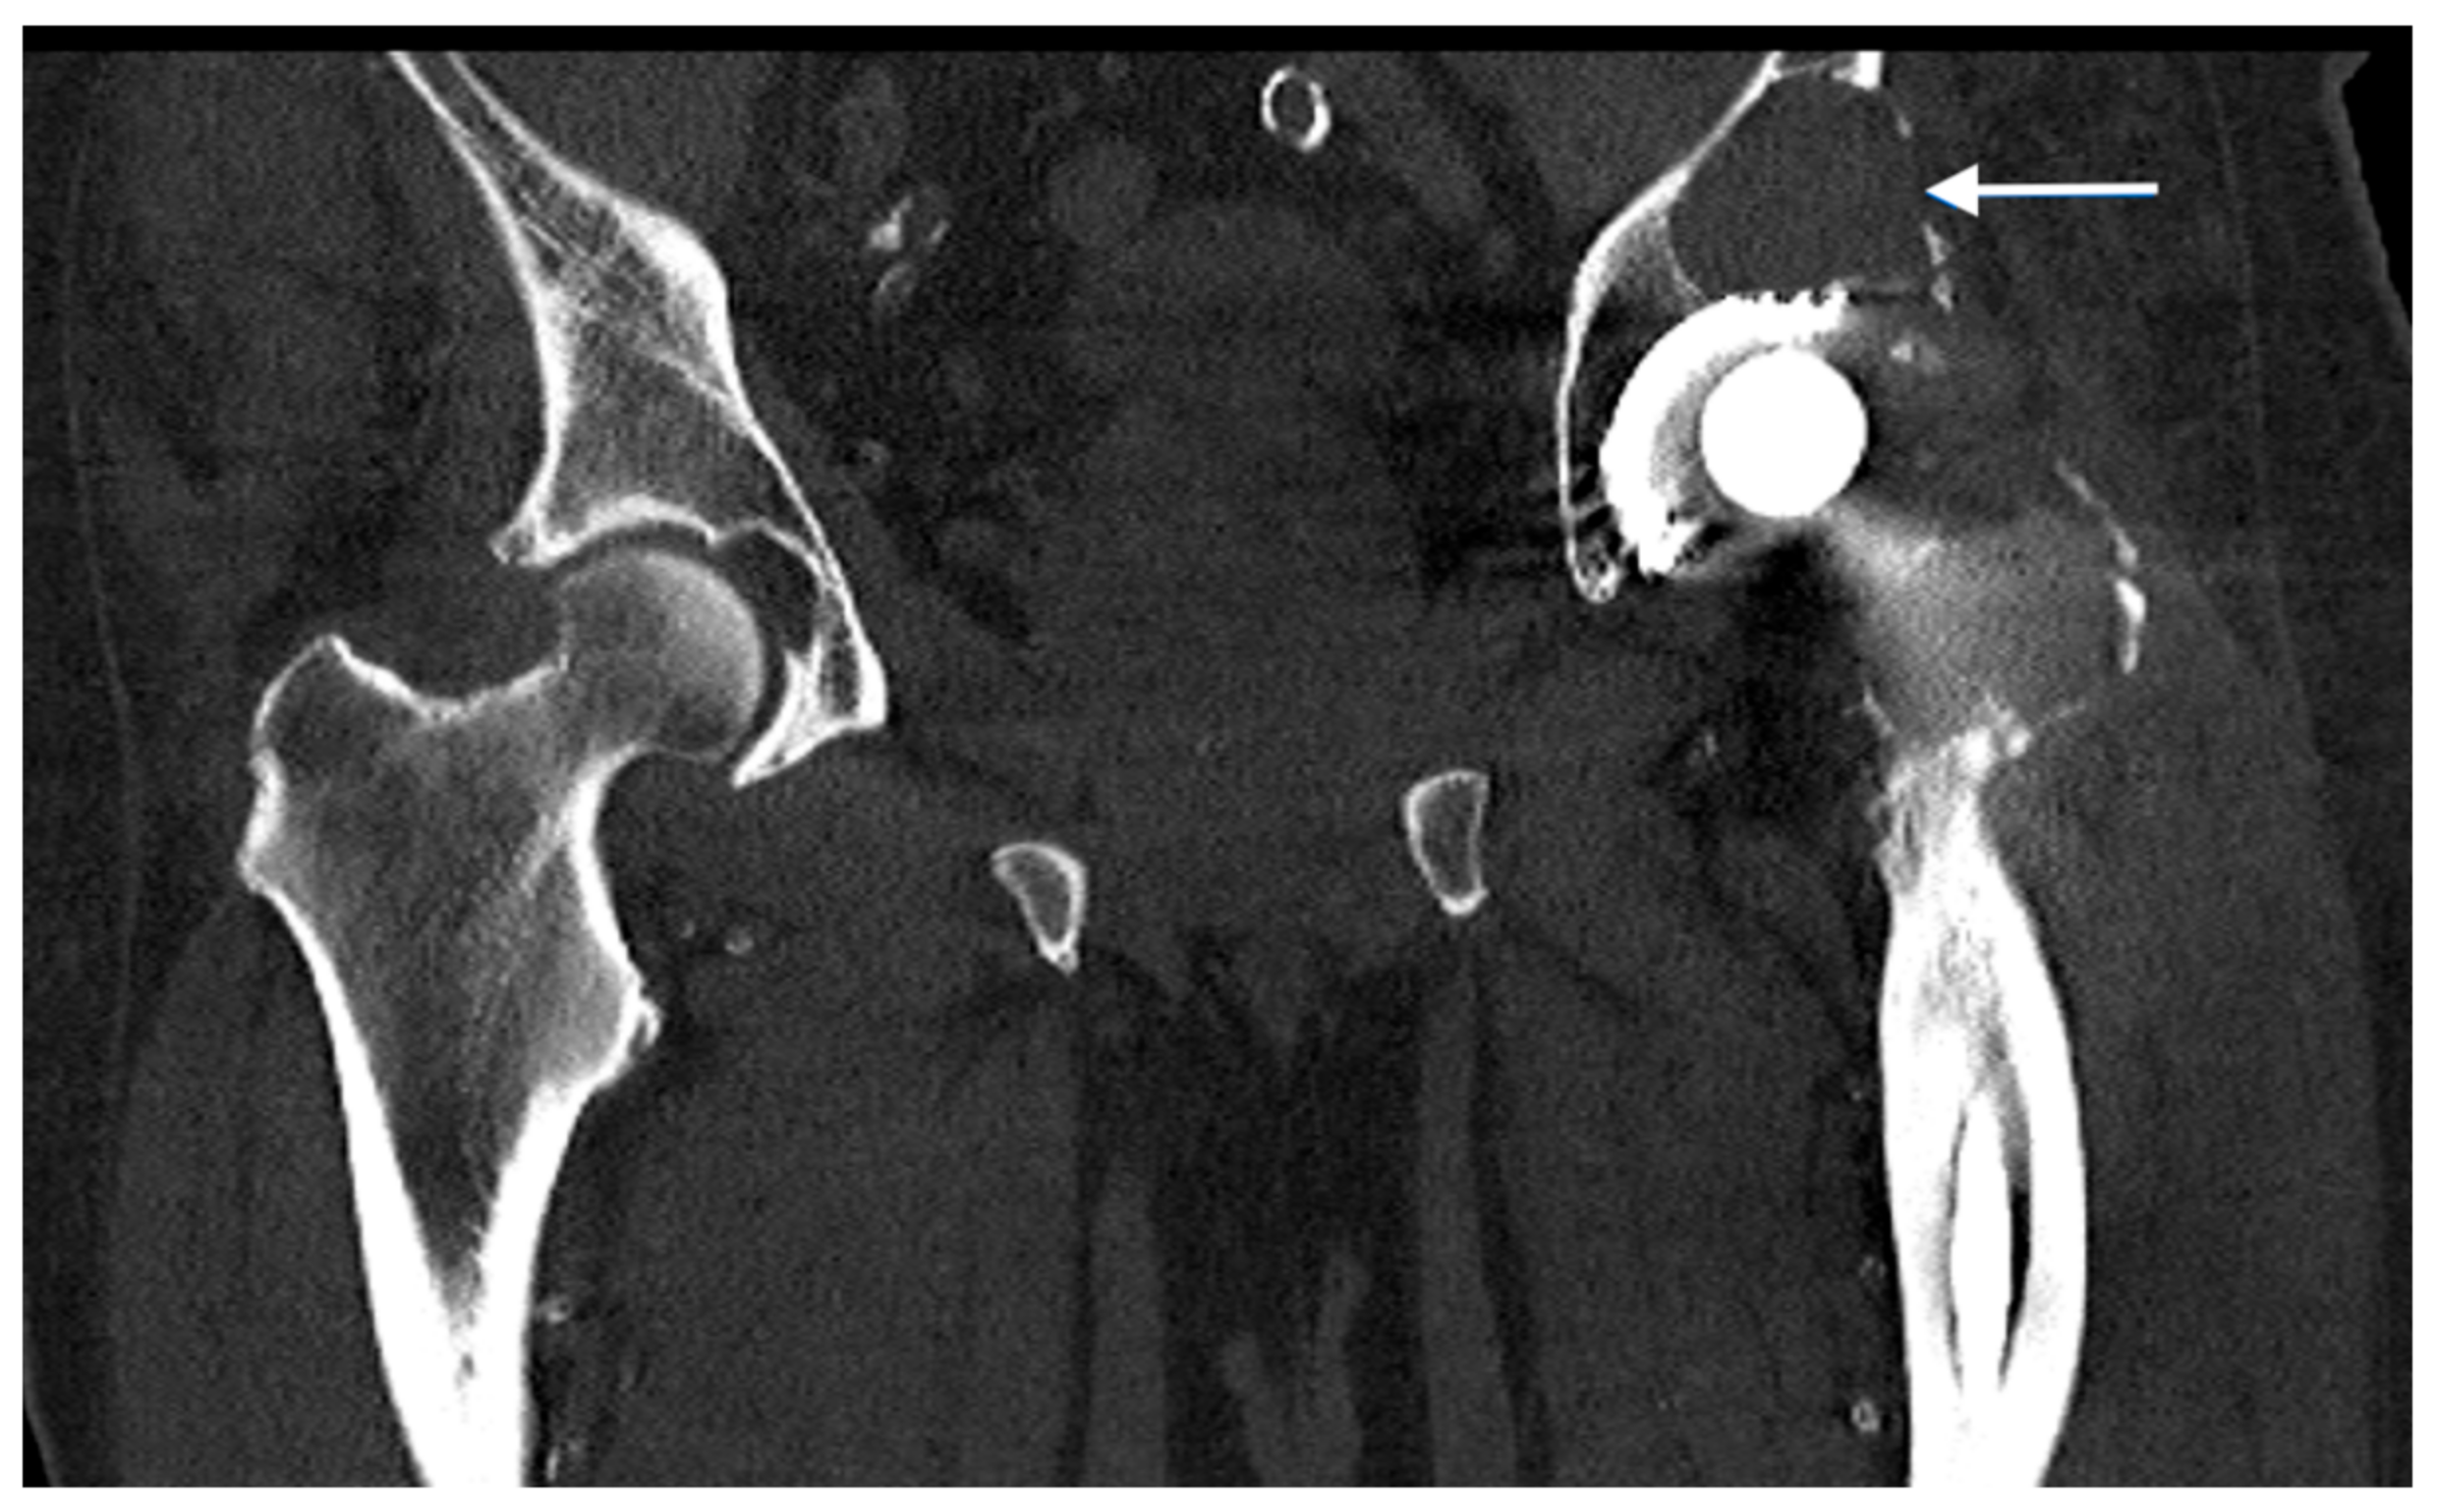

Figure 1. Computed tomography of a patient with an aseptic loosening of a hip endoprosthesis and an acetabular abrasion granuloma (indicated by the white arrow).